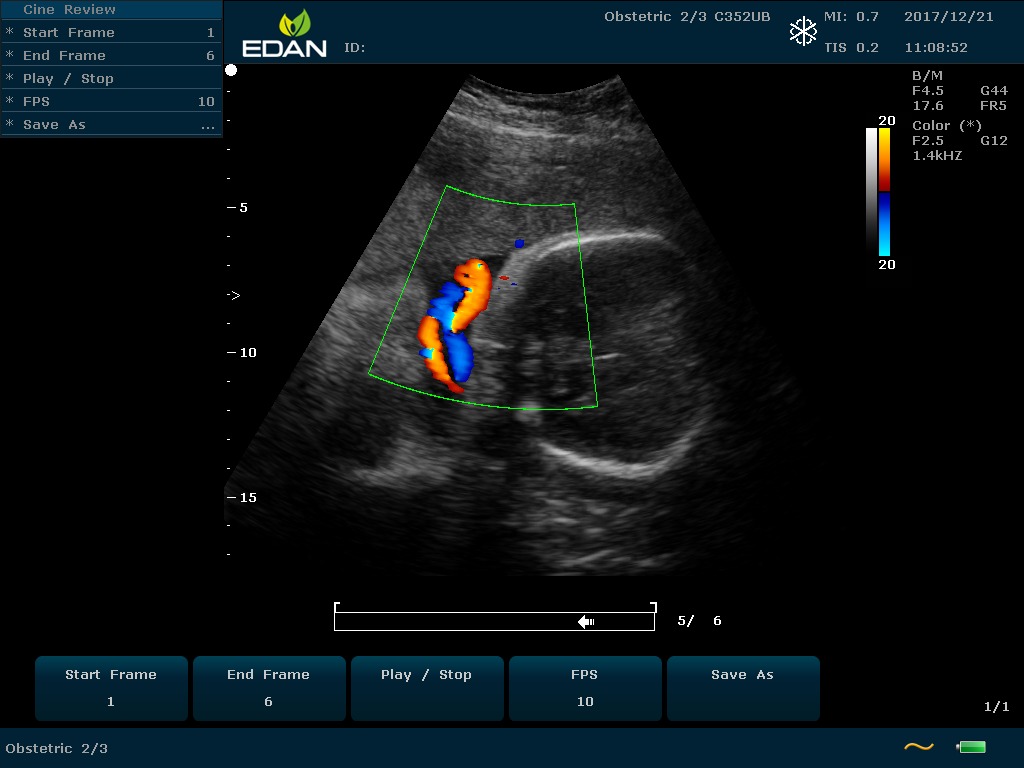

Особенность U60 Edan — расширенное применение. Ультразвуковой аппарат рекомендован для абдоминальных исследований, гинекологии и акушерства, кардиологии, педиатрии, урологии, изучения малых органов, сосудов. Для U60 Edan используются конвексные, линейные, фазированные и внутриполостные датчики.

Передовые технологии позволяют повысить качество визуализации в несколько раз. УЗИ-аппарат U60 Edan отличается возможностью быстрой настройки визуализации. Специальные функции позволяют моментально отображать данные за счет быстрой оптимизации параметров. Режимы визуализации: B-mode, M-mode, Color Doppler, Power Doppler Imaging, Pulsed Wave Doppler, Continuous Doppler.

• Цветовое Допплеровское картирование